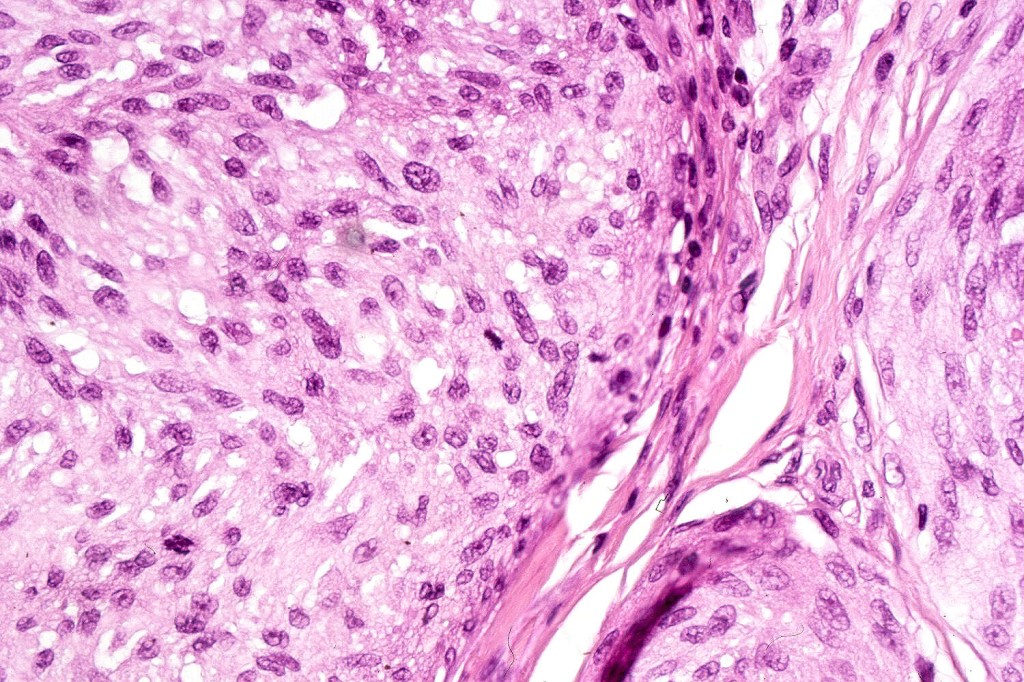

•Junctional nests often vertically orientated, dyscohesive with a surrounding retraction artifact

•Pleomorphism is almost invariable but affects all of the population to the same extent i.e., the cells & nuclei all look very much the same

•Spindle cell nests often display a “raining down” growth pattern

•Spindle cells have abundant cytoplasm and vesicular nuclei with small nucleoli

•Epithelioid cell variants often show greater pleomorphism and cells can frequently appear bizarre with abundant, sometimes ground glass cytoplasm and large vesicular nuclei with prominent eosinophilic nucleoli, multinucleate cells are often seen

•Intracytoplasmic pseudoinclusions commonly present in epithelioid cells

•Kamino bodies (often multiple) are a characteristic feature